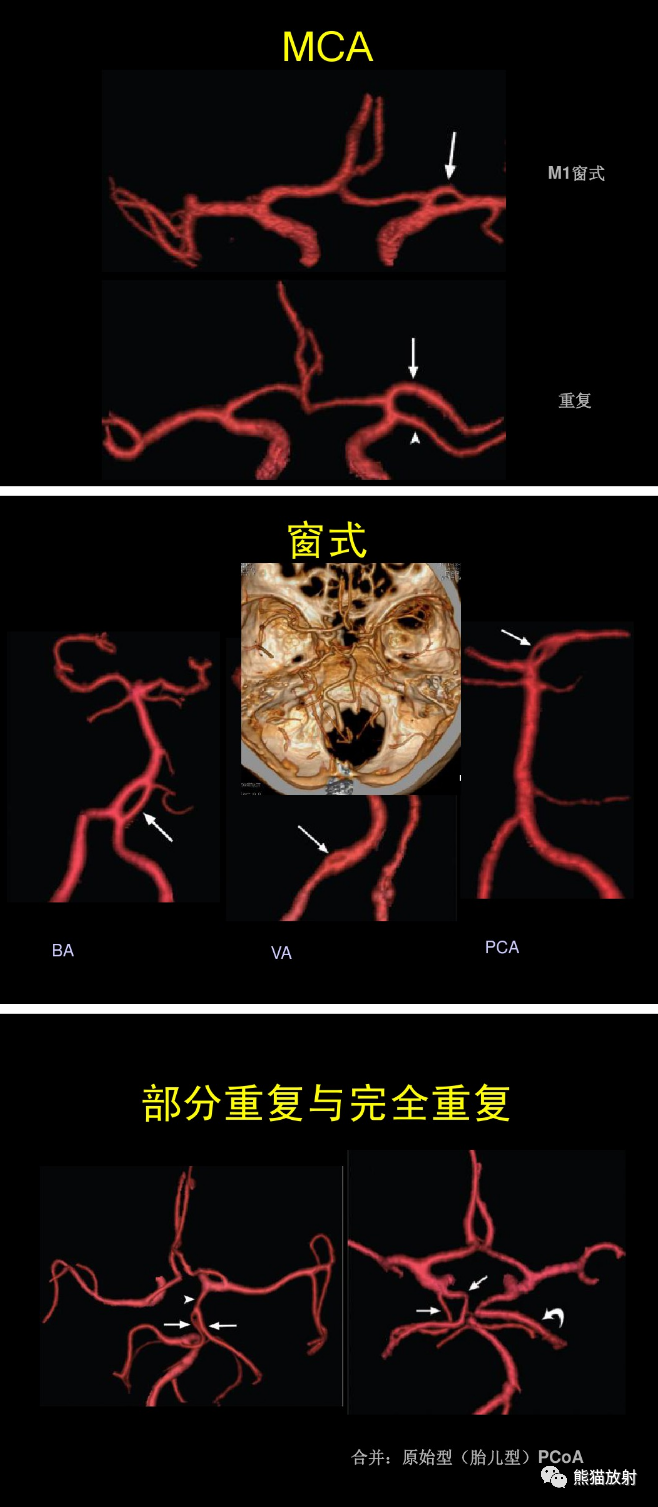

大脑前动脉 ACA,大脑中动脉 MCA,大脑后动脉 PCA,前交通动脉 ACoA,后交通动脉 PCoA,颈内动脉 ICA